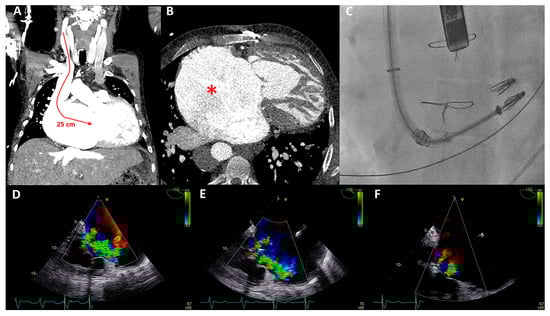

Figure 3.

(A) Color Doppler apical four-chamber view shows torrential tricuspid regurgitation (TR) with a wide vena contracta (arrow) and flow disturbance filling the enlarged right atrium. (B) Continuous wave doppler showing a dense TR signal with elevated right ventricular pressures. (C) Noncoaptation of the tricuspid valve (TV) leaflets (arrow) and annulus dilatation (dash line, 53 mm) is seen. (D) The hepatic vein Doppler demonstrates a pattern in atrial fibrillation with a prominent and late peaking systolic reversal (SR) wave. The only forward flow is evident in diastole (D-wave). (E) Two TR jets (a vena contracta of 4 and 7 mm, respectively, ERO of 90 mm2, regurgitant volume of 98 mL) are evident during transesophageal imaging. (F) Left anterior oblique and (G) right superior oblique fluoroscopic views showing patent right coronary artery (asterisk) and 18 anchors (arrows) between the two TV commissures allowing the Cardioband to significantly reduce the annulus dimensions. (H) Transesophageal echocardiography showing significant reduction in TR after the Cardioband annulus reduction procedure (appreciate the difference with panel (E), vena contracta of 3 and 5 mm, respectively, ERO 35 mm2, regurgitant volume of 41 mL).

The patient underwent a successful Cardioband annular reduction using right venous femoral access under general anesthesia with fluoroscopic (selective cannulation of the right coronary artery) and TEE guidance (Figure 3E–H). A total of 18 anchors were placed between the anteroseptal and posteroseptal commissure reducing the annulus dimensions to 45 × 36 mm. The torrential TR (two jets) was reduced to moderate TR (Figure 3E,H). At two years follow-up, the patient was in NYHA functional class I-II and no heart-failure-related admissions occurred. His NT-proBNP serum levels decreased to 2762 ng/L and at echocardiography he had a stable moderately reduced RV function and moderate TR.